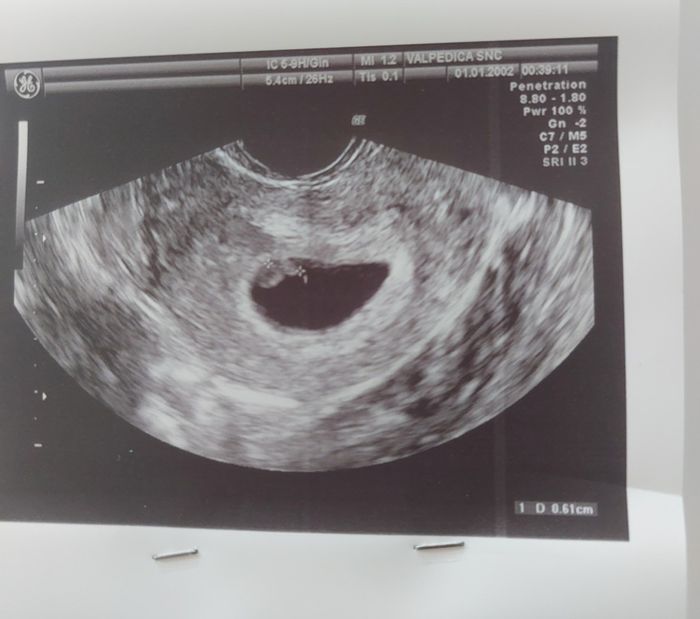

Ciao ragazzeeee ho visto che qualcuna di voi riesce con questo metodo a ipotizzare il sesso… Eco esterna a 7+5, cos’è secondo voi? 🩷💙Metodo Ramzi 1

Metodo Ramzi 2

Secondo voi maschietto o femminuccia?🥰 ecografia interna

Tesoro lo so... è un metodo che ho visto usare nelle primissime settimane, più un gioco che altro, in cui si dice il sesso in base a dove si è annidato l'embrione.. si chiama metodo Ramzi Smiley heart

io il suo metodo l'ho letto, ovvero quando la placenta si trova sul lato destro sarà un maschietto mentre se si trova sul lato sinistro sarà una femminuccia, però io vedendo la tua non riesco a capire Smiley xd